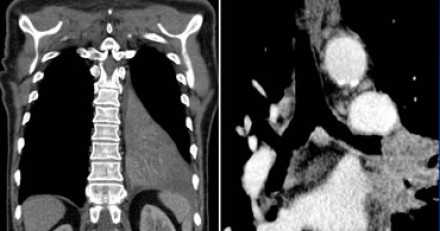

- Т3 - опухоль от 51 до 70 мм в диаметре в наибольшем измерении, или прямая инвазия в:

- грудную стенку (включая париетальную плевру и опухоли верхней борозды)

- диафрагмальный нерв

- париетальный перикард

- или определяются метастатические опухолевые узлы или узел в патологически измененной доле

![]()

- Т4 - опухоль более 70 мм в диаметре в наибольшем измерении, или поражение:

- диафрагмы

- средостения

- сердца

- крупных сосудов

- трахеи

- возвратного гортанного нерва

- пищевода

- тела позвонка

- бифуркации трахеи

- висцерального перикарда

- метастатические узелки (узел) в других ипсилатеральных долях

Courtesy of Wouter van Es, MD. St. Antonius Hospital Nieuwegein, The Netherlands